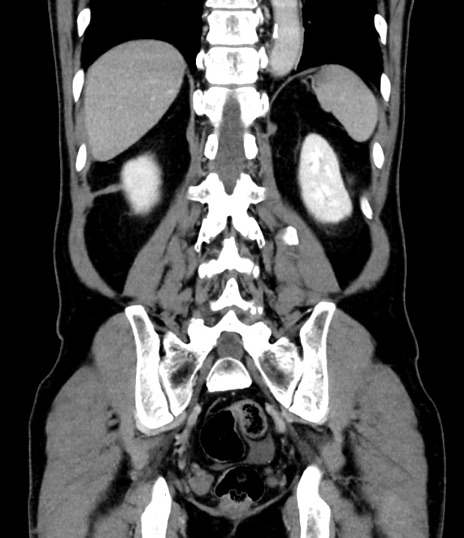

症例8(冠状断像)

【症例】 60歳代男性

【主訴】 黒色吐物

【現病歴】 4日前から嘔気自覚、2日前の朝食後にも嘔気あり、自分で手で嘔吐反射起こし嘔吐したところ血が混ざっていたため受診。

【既往歴】 5年前汎発性腹膜炎を伴う急性虫垂炎で手術、高血圧、前立腺肥大症、高脂血症

【身体所見】 腹部正中に手術癩痕あり 腹部平坦・軟圧痛なし膨満感あり

【データ】WBC 8400、CRP 4.54